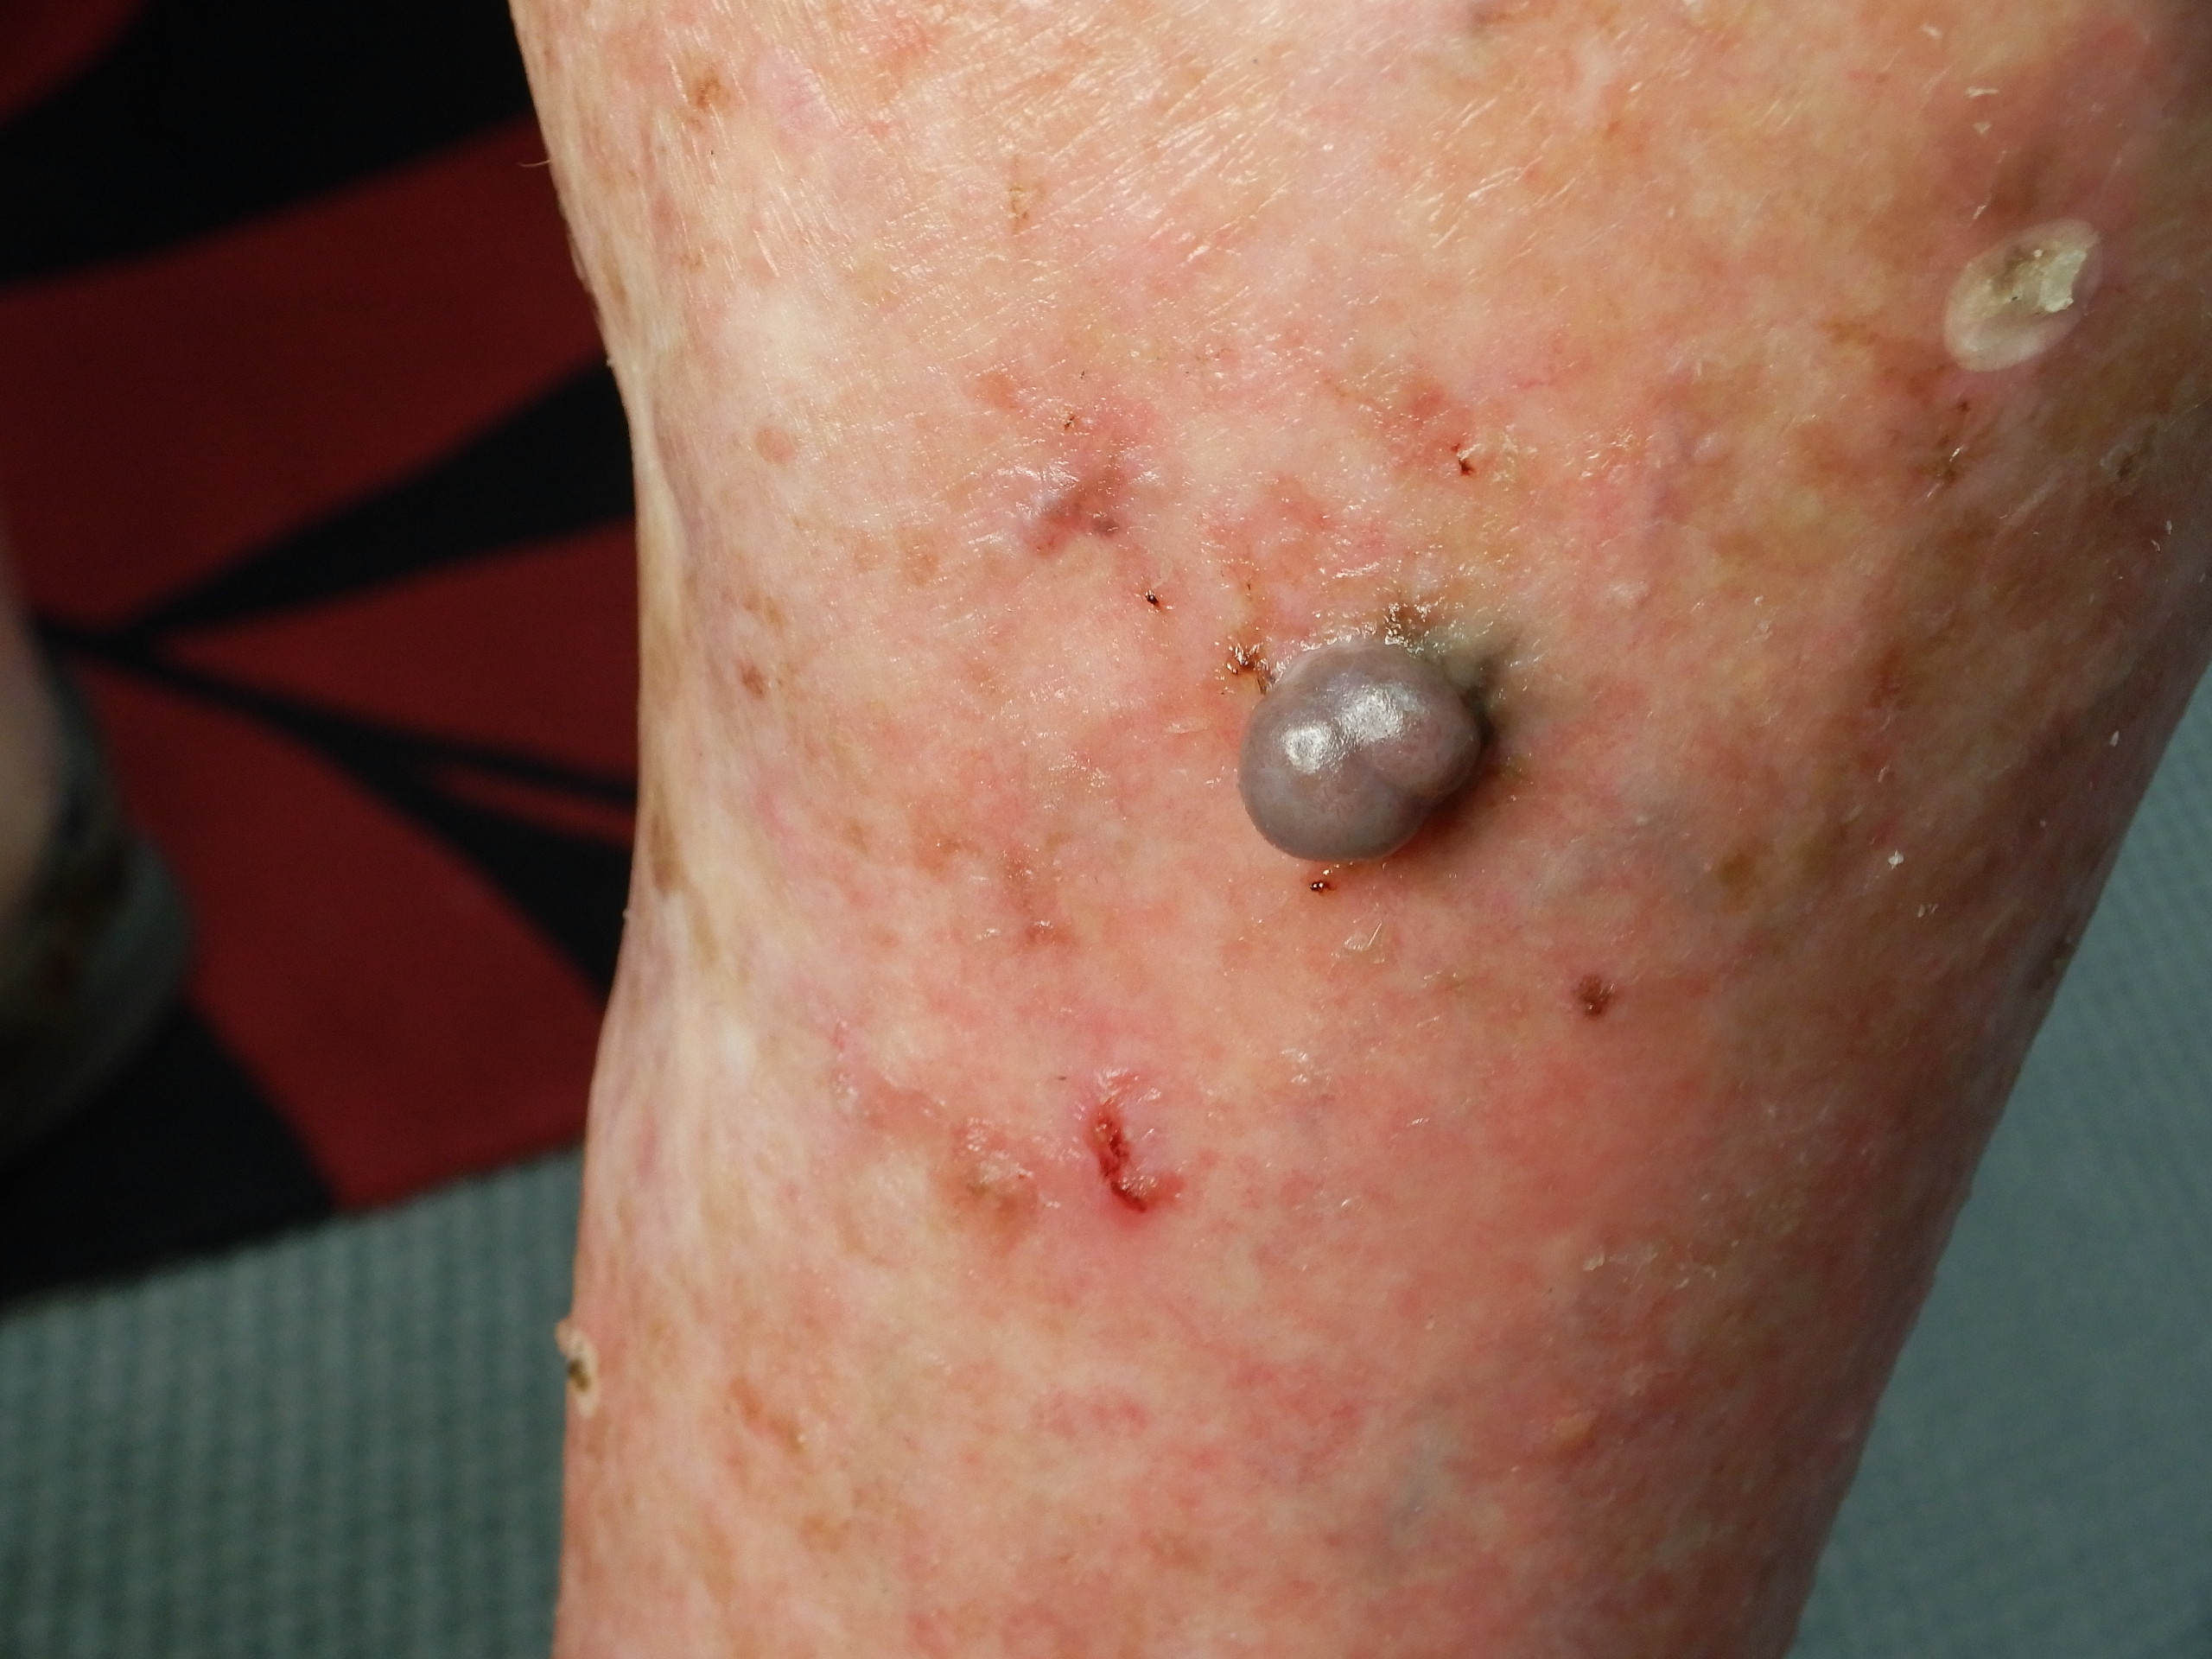

Site: Shins

Diagnosis: Melanoma nodular

Description: Blue grey nodule on the shin

Past history of several melanomas including a blue nevus like melanoma metastasis. Rapid growth over 6 weeks of this blue grey nodule on the shin. No local glands in groin. This was a 6 mm thick pigmented nodular melanoma. Compare it with the previous case.